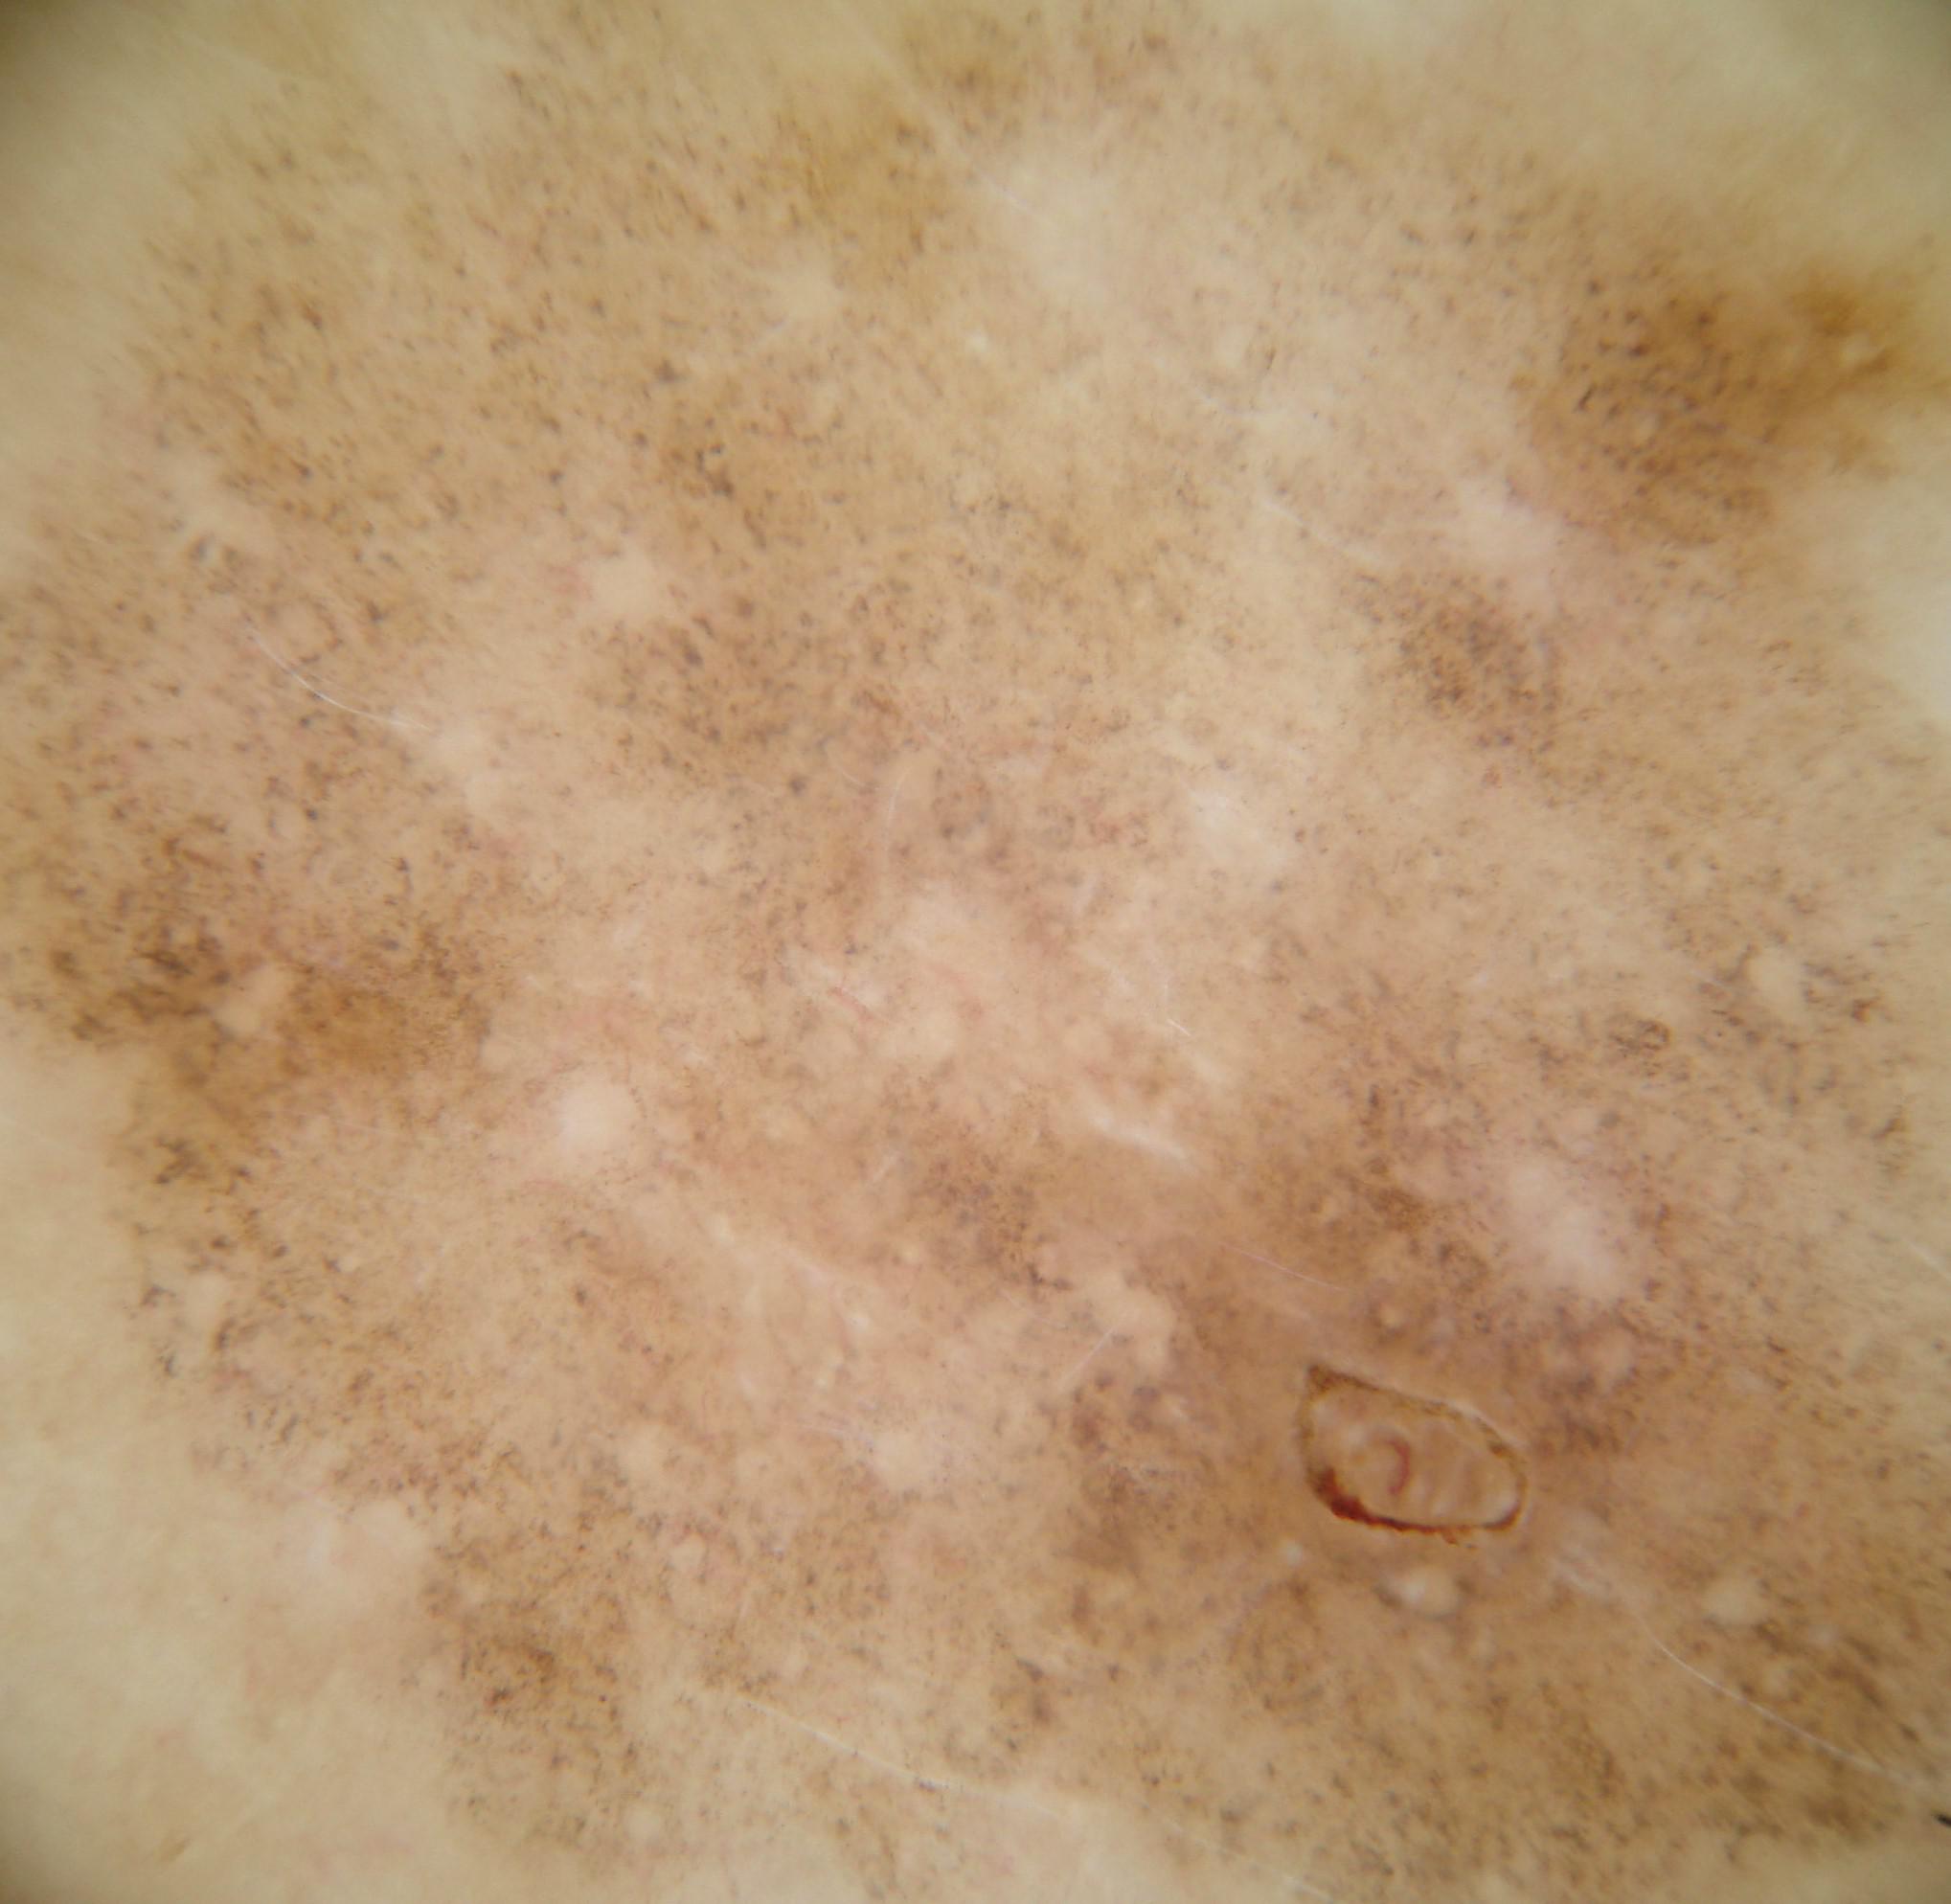

{

"age_approx": 35,

"anatom_site_general": "posterior torso",

"concomitant_biopsy": true,

"dermoscopic_type": "non-contact polarized",

"diagnosis_1": "Benign",

"diagnosis_2": "Benign melanocytic proliferations",

"diagnosis_3": "Nevus",

"diagnosis_4": "Nevus, Atypical, Dysplastic, or Clark",

"diagnosis_5": "Nevus, Clark",

"diagnosis_confirm_type": "histopathology",

"family_hx_mm": false,

"image_type": "dermoscopic",

"melanocytic": true,

"patient_id": "IP_6338367",

"personal_hx_mm": true,

"sex": "male"

}